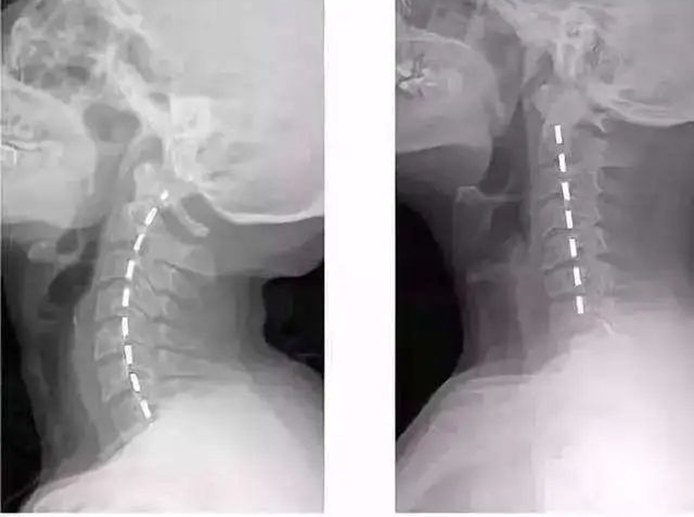

牵引角度包括前屈位、中立位和后伸位,即牵引绳分别位于头部的斜前方、正上方和后上方,其中,前屈位牵引最为常见。在治疗中,一般先根据影像资料找到发生病变的颈椎节段,再确定牵引的位置与角度。

颈椎共有7节

牵引时要将下巴和后脑勺包住,图为前屈位牵引中不同的牵引角度